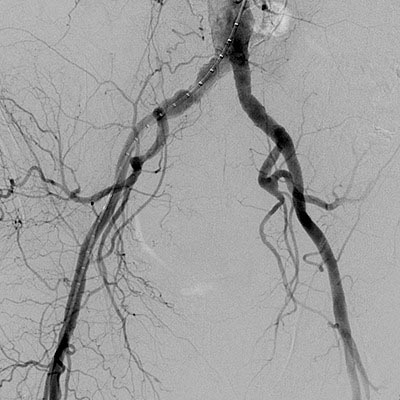

La patología vascular, esa amplia categoría de enfermedades que abarca los trastornos de los vasos sanguíneos, ya sean arterias o venas, es motivo de profunda preocupación en el ámbito…